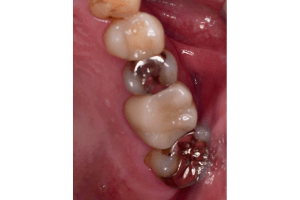

年齢・性別 40代・男性

主訴 銀歯を白くしたい

治療方針 金属を使った詰め物、被せ物を外して、セラミックでの詰め物、被せ物にやりかえたいというご要望がありました。

奥歯はほとんどの歯に詰め物が入っていましたので、まずは奥歯から噛み合わせをきちんと作ってから前歯の被せ物をやりかえていく方針としました。

また、左下の奥から1番目の歯は虫歯が大きいことをレントゲンで確認できており、神経を取り除かねばならない可能性が高いことを説明してから、治療をおこなっていきました。

治療内容 左下の奥から2番目の歯は、やはり神経を取り除く必要がありました。その他の奥歯の部位は詰め物のやり変えのみですみました。 前歯は金属の土台(メタルコア)も取り除き、セラミックとジルコニアでできた被せ物を入れていきました。

奥歯の詰め物の治療終了後

奥歯の治療が終わったところです。前歯の治療に行く前に、噛み合わせをしっかり確認します。